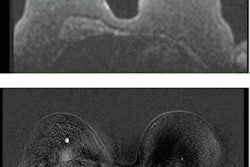

Extremely dense breast tissue is a risk factor for breast cancer and limits the detection of cancer with mammography, explained Marije Bakker, PhD, and fellow authors of the 2019 NEJM paper about the DENSE trial.

Evidence was needed on the use of supplemental MRI to improve early detection and reduce interval breast cancers in such patients. During a two-year screening period, the use of supplemental MRI screening in women with extremely dense breast tissue and normal results on mammography resulted in a significant reduction of interval cancers (80%) and the detection of small tumors with less lymph node metastases compared with mammography alone, they reported.